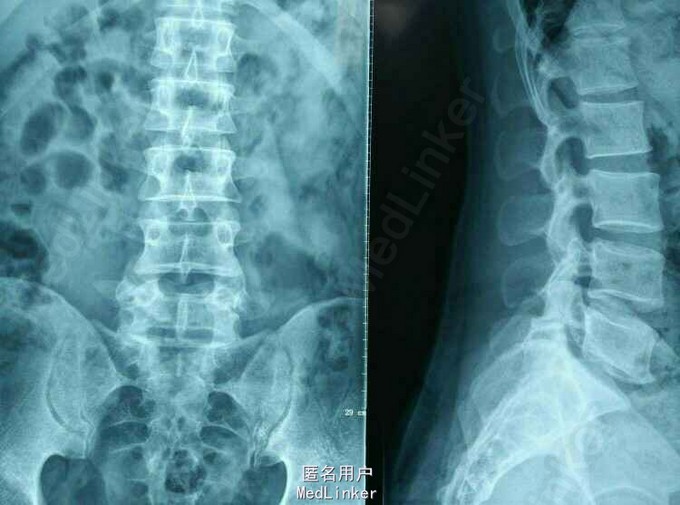

患者,男,42岁,因“腰痛伴右下肢放射痛麻木1周”入院。入院查体:L5S1椎间隙压痛,右侧小腿后侧及外侧感觉减退,右足拇指背伸肌力力足跖屈肌力IV级,右下肢直腿抬高30度阳性。

MRI及CT:L5S1 椎间盘脱出,向上游离。